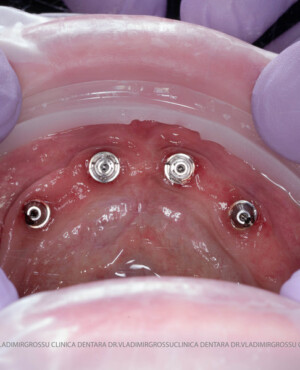

studii științifice.În cazurile de atrofie osoasă severă, când inserarea implanturilor în zonele laterale nu este posibilă fără adăugare osoasă, conceptul All-on-4 prevede plasarea implanturilor în unghiuri strategice pentru a evita zonele deficitare. Astfel, două implanturi sunt plasate în zona incisivilor laterali, iar alte două în zona premolarilor.

- 4 implanturi;

- 2 multiunit-uri drepte și 2 multiunit-uri angulate, conform necesităților protetice;